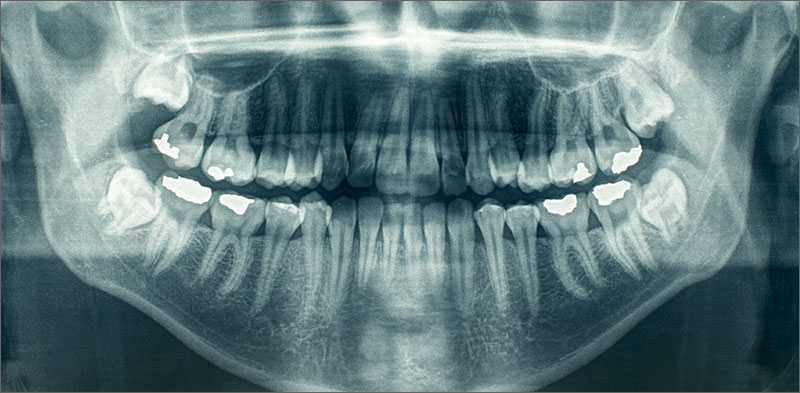

X-rays help your dentist see diseases in your teeth and other oral structures that he cannot see through an oral exam. Many oral diseases start well beneath the surface of your teeth or gums, long before you see signs on the visible surfaces of your mouth. For this reason, X-rays help you gain the early treatment you need, saving you a great deal of time, money, and discomfort.

Dental X-rays help your dentist see many problems, including:

• Decayed areas between or behind teeth

• Decay beneath fillings

• Bone loss occurring because of gum disease

• Changes in your bones or root canals

• Abscess infections

• Cysts, tumors, and other abnormalities